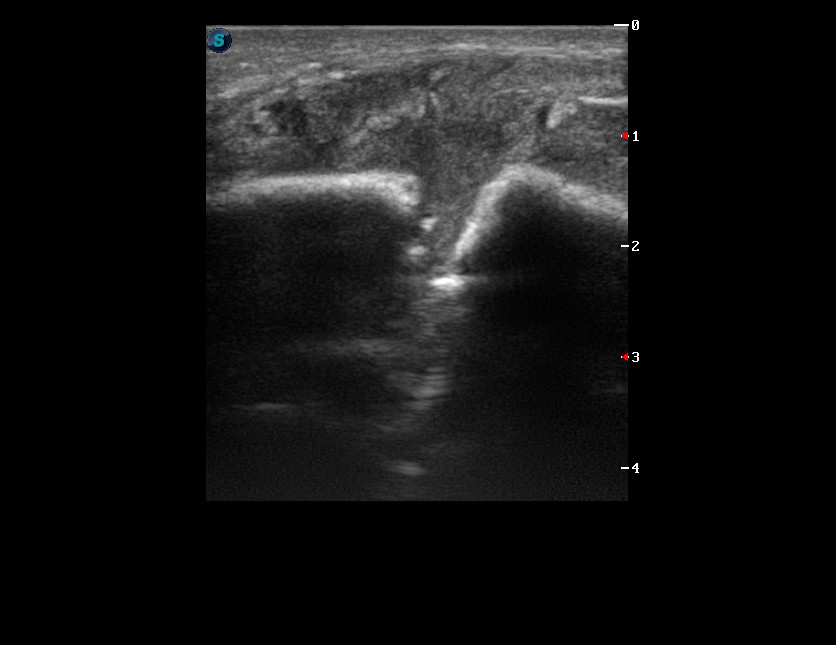

Молодой парень с припухлостью в области угла левой нижней челюсти.

Прислал ЛОР провести дифдиагноз между лимфаденитом и сиаладенитом.

--Травма была?

--ЫЫЫ. Месяц назад...